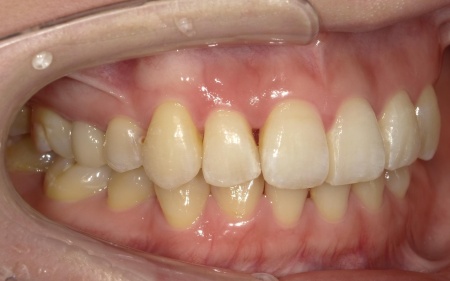

拝見したところ、叢生(そうせい)が上下前歯に確認できました。

今回のケースでは上前歯にやや目立つ重なりがあり、下前歯は軽度の叢生が見られました。

一方で奥歯の噛み合わせについては、大きなズレや機能的な問題はありませんでした。